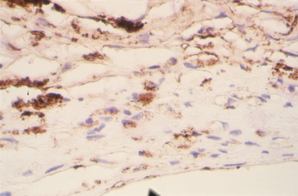

Figure 2. Immunostained surgically-excised inflammatory inactive CNV

A: Inflammatory inactive CNV with more fibrosis than inflammatory cells. (hematoxylin and eosin, 25x) B: There are rare macrophages and fibrocytes in the stroma expressing VEGF. (peroxidase anti-peroxidase, 63x) C: There are rare cells in the stroma, mainly macrophages, expressing TF. (peroxidase anti-peroxidase, 63x) D: Negative control. (peroxidase anti-peroxidase, 63x)